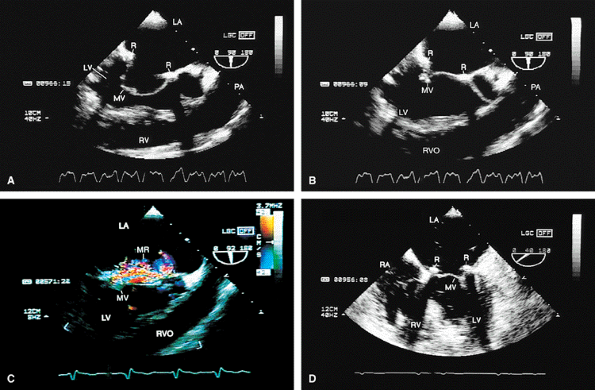

FIGURE 5.16. Mitral annuloplasty ring: obstruction. A,B. Prominent diastolic flow acceleration (arrow) and a narrow inflow jet resulted from obstruction produced by a Duran ring in this patient. LA, left atrium; LV, left ventricle; MV, mitral valve; RA, right atrium; RV, right ventricle. |